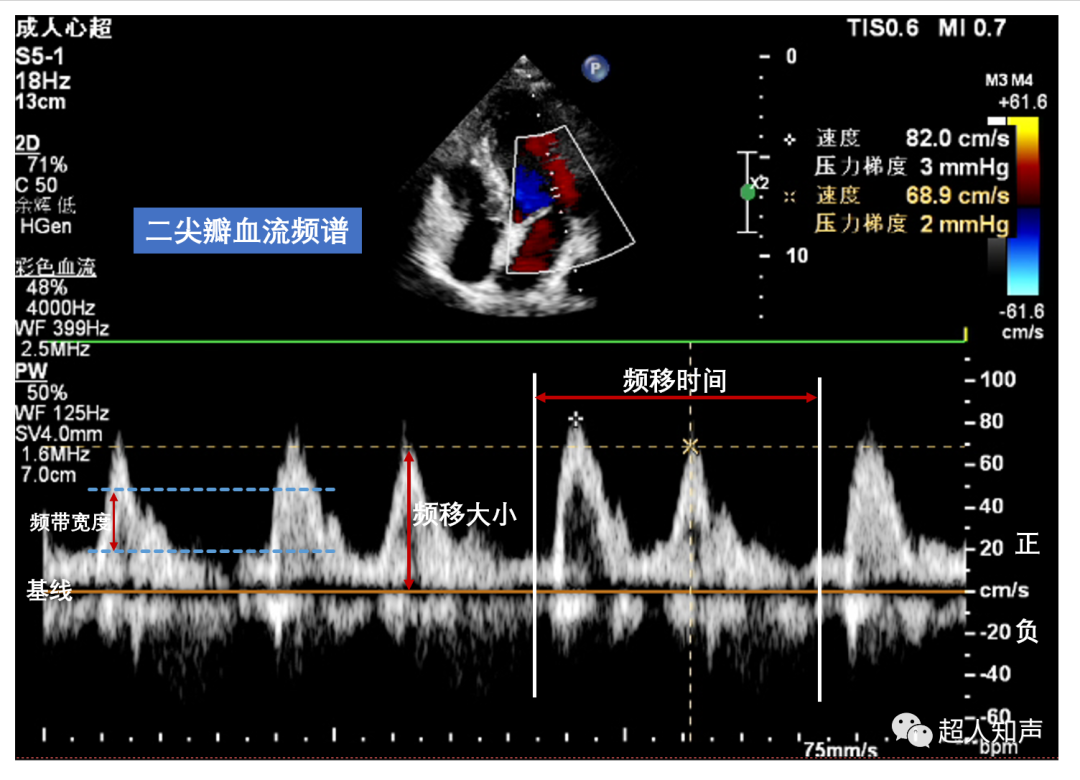

1.零位基线上方的波形:表示血流朝探头方向流动,而基线下方则为血流背向探头方向流动。

2.“横坐标”:即频移时间,表示血流出现和持续时间。

3.“纵坐标”:即频谱大小,表示血流速度大小。

4.频谱宽度(频带宽度):频谱在“纵坐标”上的宽度,表示在某一时刻取样门中红细胞运动速度分布范围的大小。频带宽,速度范围大;频带窄,速度范围小。